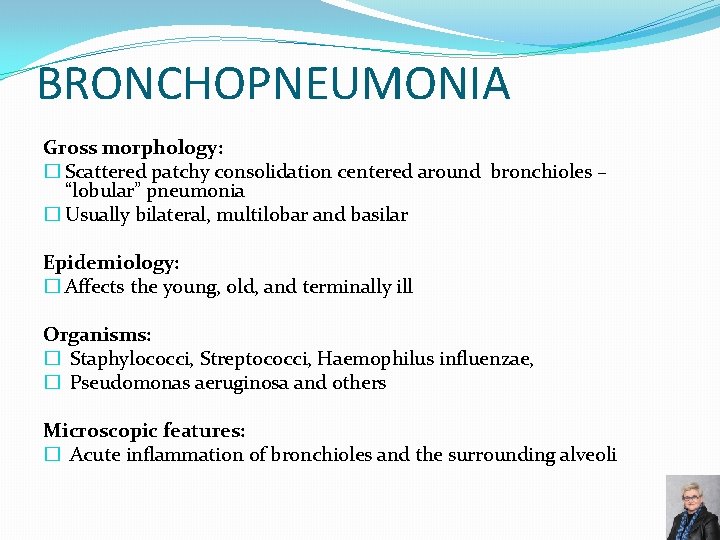

BRONCHOPNEUMONIA Gross morphology: � Scattered patchy consolidation centered around bronchioles – “lobular” pneumonia � Usually bilateral, multilobar and basilar Epidemiology: � Affects the young, old, and terminally ill Organisms: � Staphylococci, Streptococci, Haemophilus influenzae, � Pseudomonas aeruginosa and others Microscopic features: � Acute inflammation of bronchioles and the surrounding alveoli 67